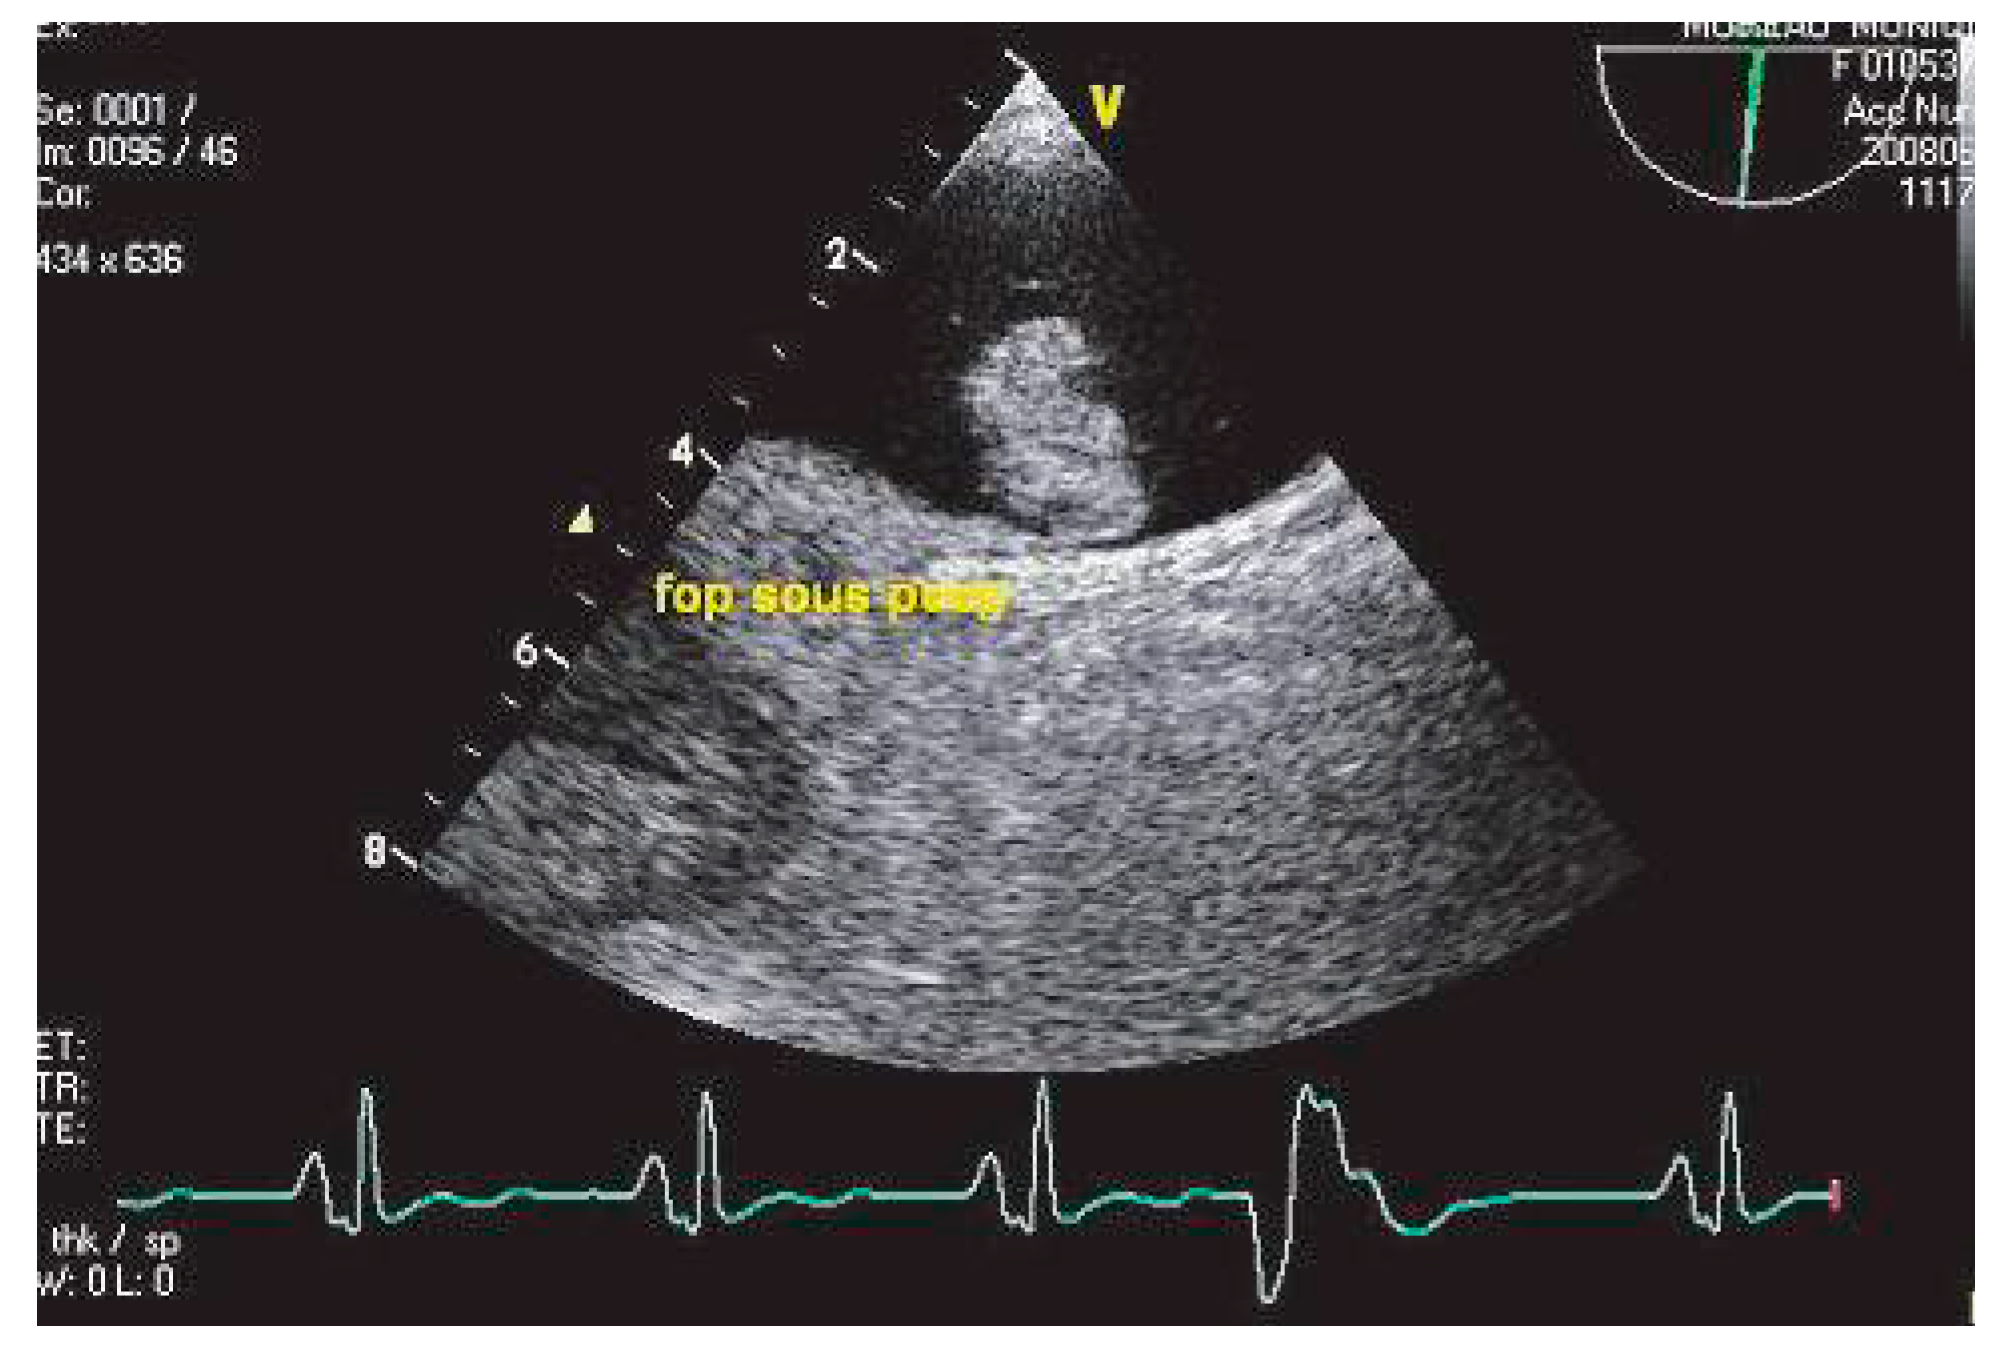

Foramen ovale perméable

Le foramen ovale perméable est défini par la présence d’un shunt à l’étage auriculaire en regard de la région de la fosse ovale (Figure 7), en l’absence de solution de continuité au sein de la membrane [55].

Figure 7. Epreuve de contraste très positive, en ETO, chez la même patiente qu’en 6, ventilée pour AIC massif.